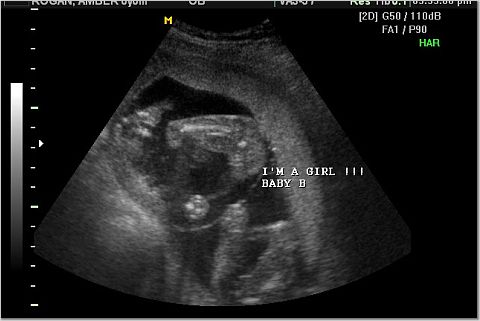

The "It's a girl" shots.

Right above the "I'm" in the first pic and to the left of the "I'm" in the second pic

are the 3 white lines that indicate girl.